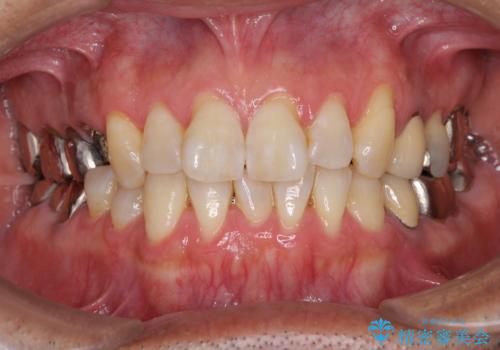

折れてしまった奥歯 インプラントによる補綴治療

- 50代男性

- 奥歯に違和感を感じており、抜歯の必要性を感じて来院された患者様です。

診査の結果、5本の奥歯を抜歯してインプラントによる補綴治療が必要と診断されました。

患者様が違和感を感じていない左下の奥歯の治療は今回は見送り、それ以外の治療が必要な奥歯を治療することとしました。